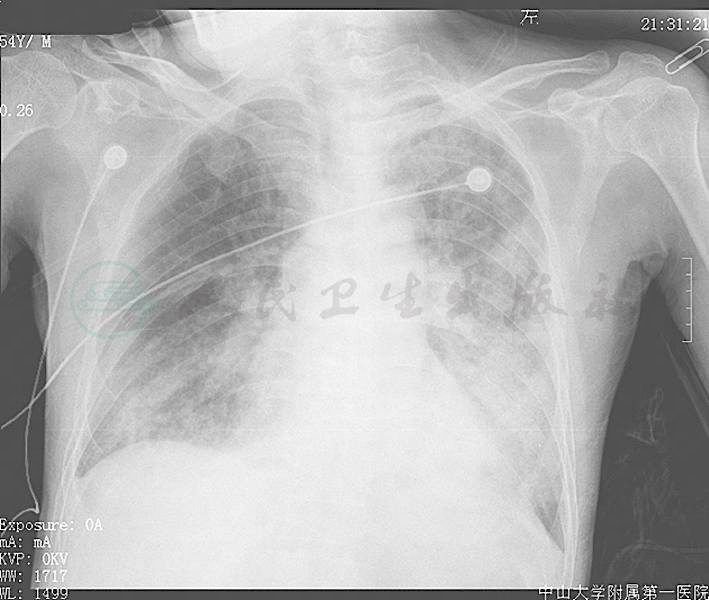

入院后予以对症支持治疗,吸氧、抗凝、抗血小板聚集、调脂、改善冠状动脉循环、营养心肌、护肾及维持水、电解质、酸碱平衡等,并行CRRT等对症治疗。完善相关检查,血常规:WBC 12.05×109/L,N 77.9%,RBC 2.79×1012/L,Hb 79g/L,PLT 207×109/L;CK-MB 32.87ng/ml,肌红蛋白420.60ng/ml,cTnT 7.630ng/ml,K+ 5.33mmol/L,Na+ 145mmol/L,Cl- 104mmol/L,CO2 27mmol/L,BUN 29.1mmol/L,CREA 591μmol/L,BUN/Cr 0.049,Glu 6.2mmol/L,Ca2+ 2.22mmol/L,BNP 141664pg/ml;出凝血常规示:APTT 26.8秒,PT 18.6秒,FBG 4.79g/L,INR 1.59;渗透压325.7mOsm/L,阴离子间隙19.53mmol/L;尿红细胞位相示蛋白(++),pH 5.5,正形红细胞55000个/ml,畸形红细胞80000个/ml;胸片示双肺渗出性病变,右下肺肺炎(图1);超声心动图:考虑冠心病合并高血压性心脏病,左右心房及左心室增大,二、三尖瓣关闭不全(轻度),左心室收缩功能减低。进一步行胸部CT:①右肺下叶肿块影,内见多发钙化灶,性质待定,建议增强扫描;②双下肺炎症;③双侧少量胸腔积液,双下肺局部压迫性肺不张,未见结核及肿瘤相关表现。与此同时,CK-MB、cTnT呈现进行性升高(见图2)。

图1 入院时的床边胸片